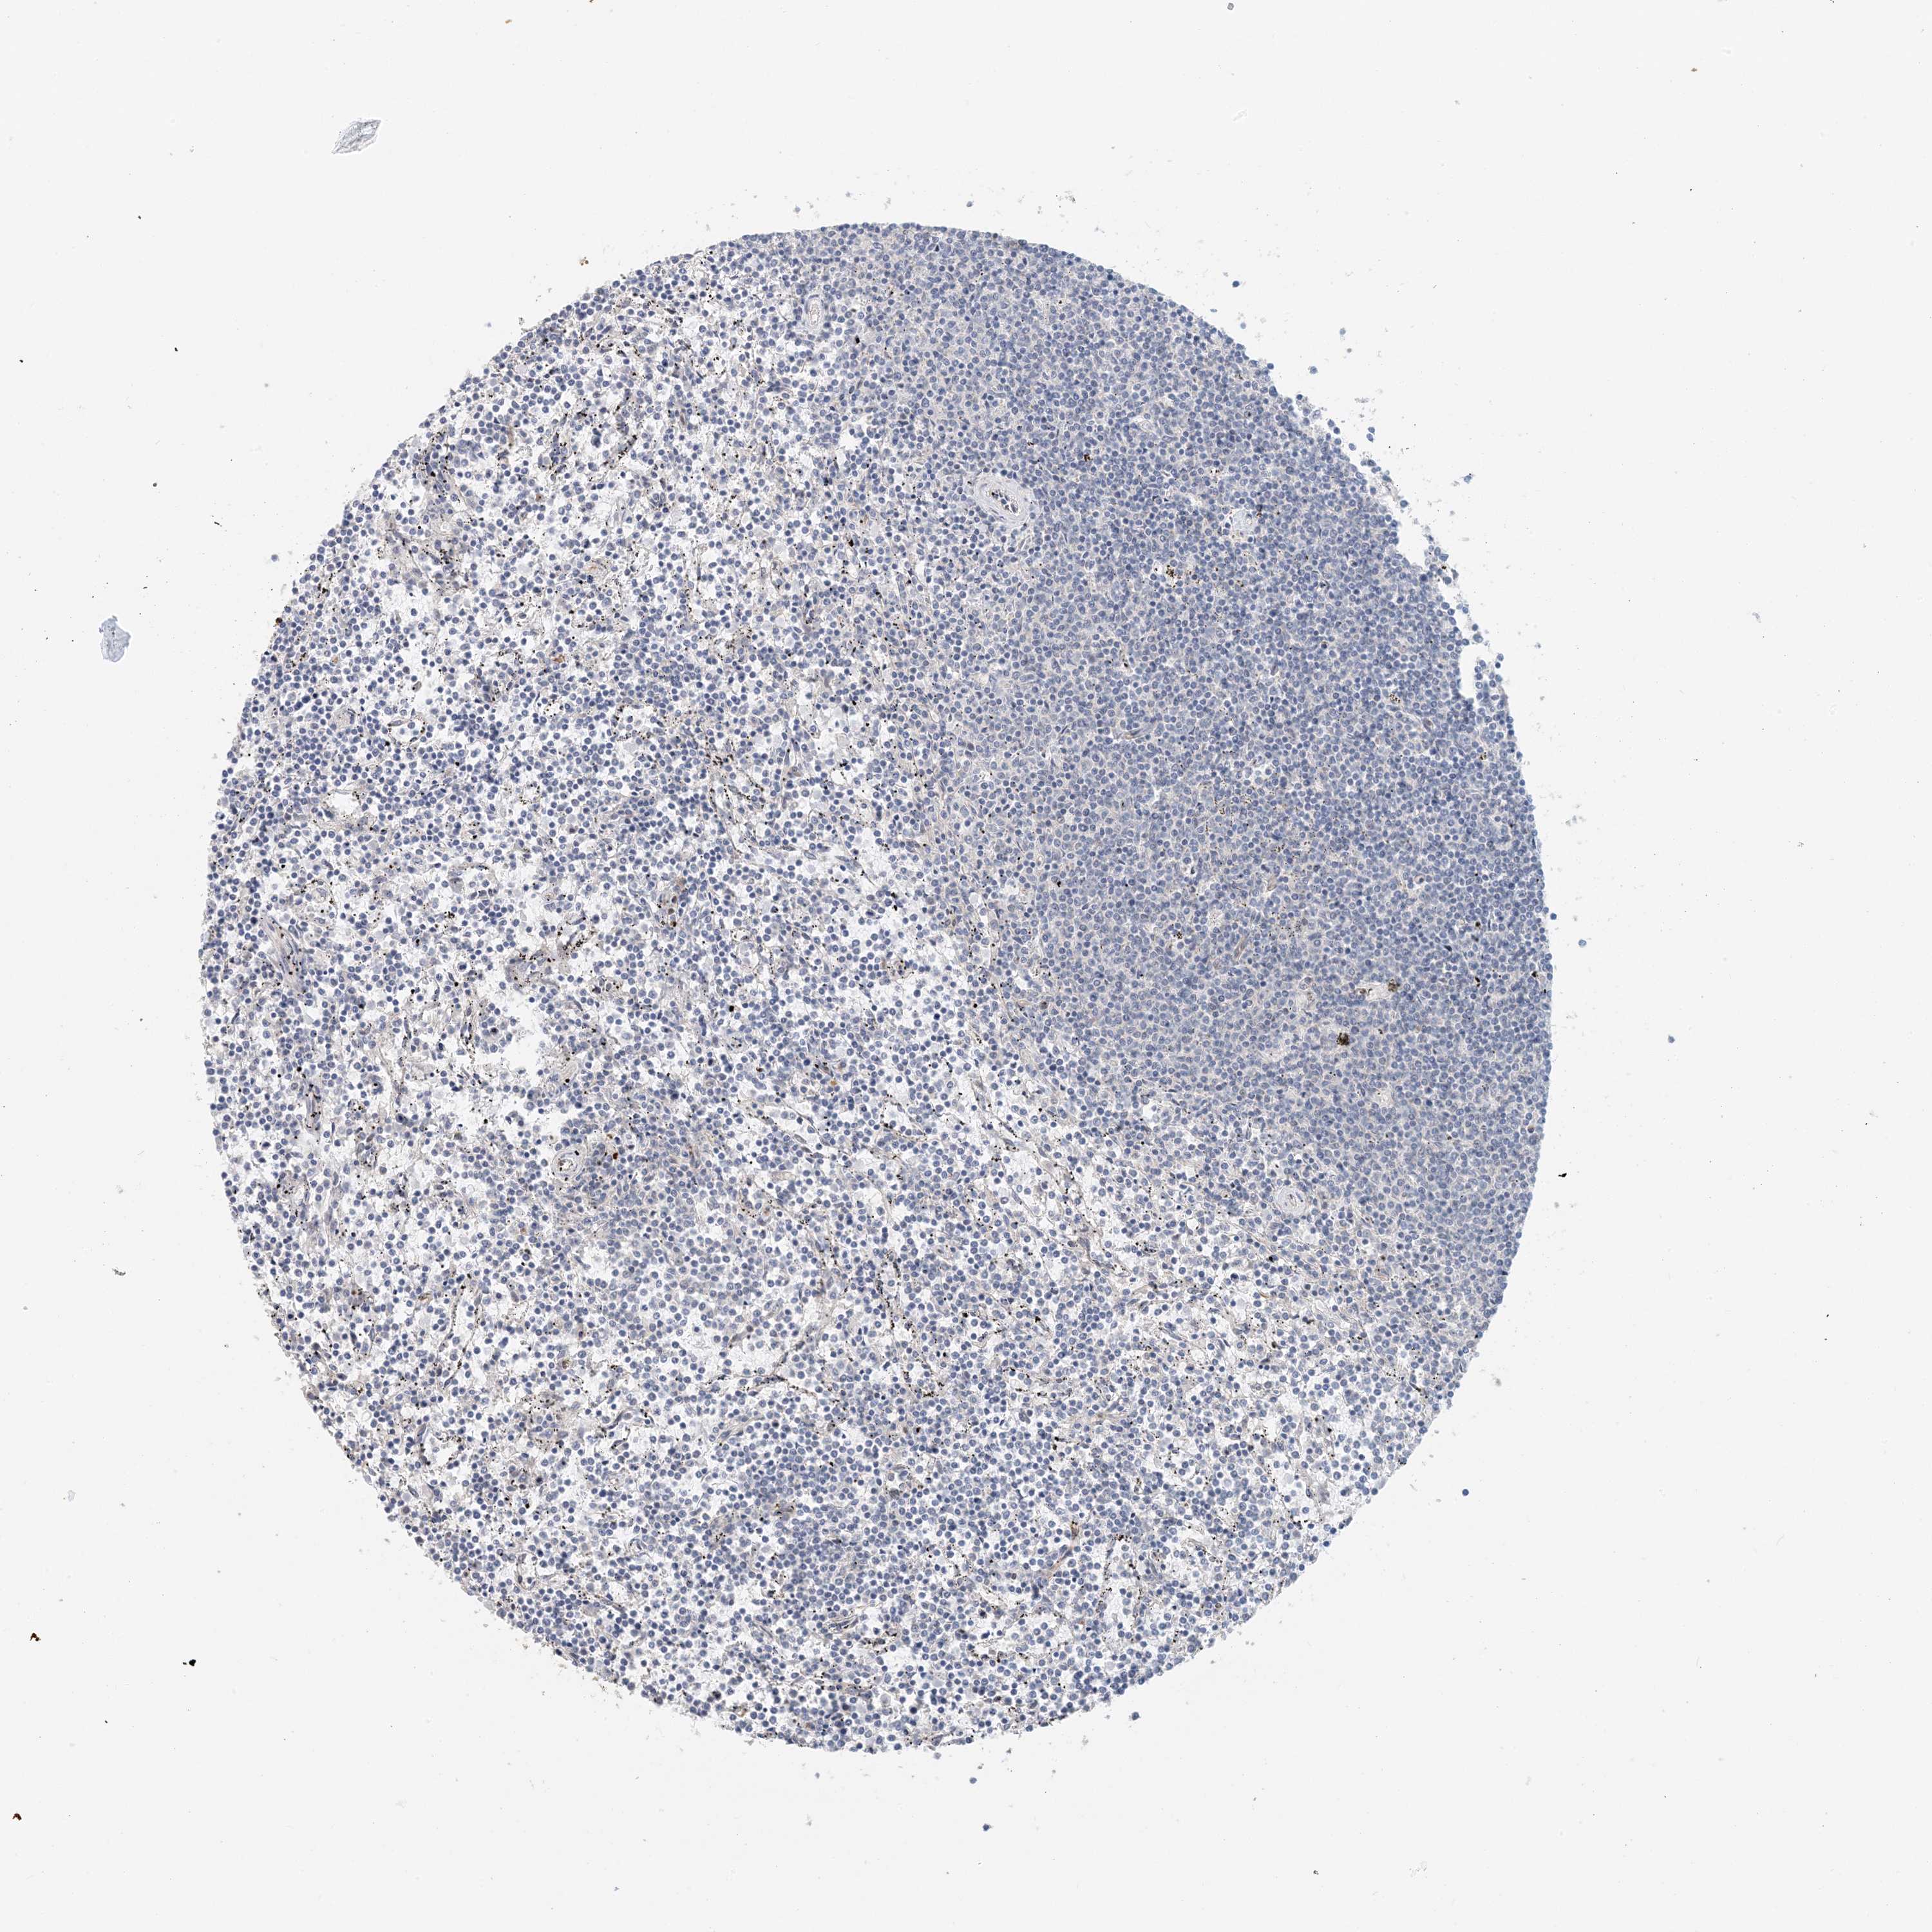

CANCER LYMPHOMA Show tissue menu

LYMPHOMA - Protein expressioni

A mouse-over function shows sample information and annotation data. Click on an image to view it in a full screen mode. Samples can be filtered based on level of antibody staining by selecting one or several of the following categories: high, medium, low and not detected. The assay and annotation is described here.

Each image is clickable and will lead to virtual microscopy that enables deeper exploration of all samples and also displays staining intensity scores, fraction scores and subcellular localization as well as patient and tissue information for each sample.

Antibody HPA035575

Antibody HPA035576

Hodgkin's disease, NOS

Malignant lymphoma, non-Hodgkin's type, High grade

Malignant lymphoma, non-Hodgkin's type, Low grade